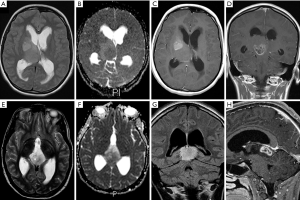

An overview of conventional imaging features is shown in Table 3. All H3 K27M-mutant gliomas were in contact with the brain midline (Figure 3). The lesion volumes ranged from 9.2 to 103.1 cm3. The definition of the non-contrast enhancing tumour margin appeared variable, whereby most lesions demonstrated heterogeneous T2/FLAIR signal. The observed T2/FLAIR heterogeneity corresponded to visible differences in ADC signal, with facilitated diffusion shown in necrotic glioma components. None of the H3 K27M histone-mutant gliomas exhibited a T2-FLAIR mismatch sign. Several tumours contained haemorrhagic components (Figure 4), whereas calcification was not identified, and only two tumours contained cysts. Rim-enhancement surrounding necrosis was present in 10/15 (67%) gliomas; 6/15 (40%) patients required shunting for hydrocephalus. Two gliomas were imaged with dynamic susceptibility contrast enhanced (DSC) perfusion MRI (Figure 5), which revealed elevated relative cerebral blood volume (rCBV) indicative of neovascularity. In one case, 18F-choline PET imaging was performed, showing radioactive tracer accumulation within enhancing tumour components (Figure 6).